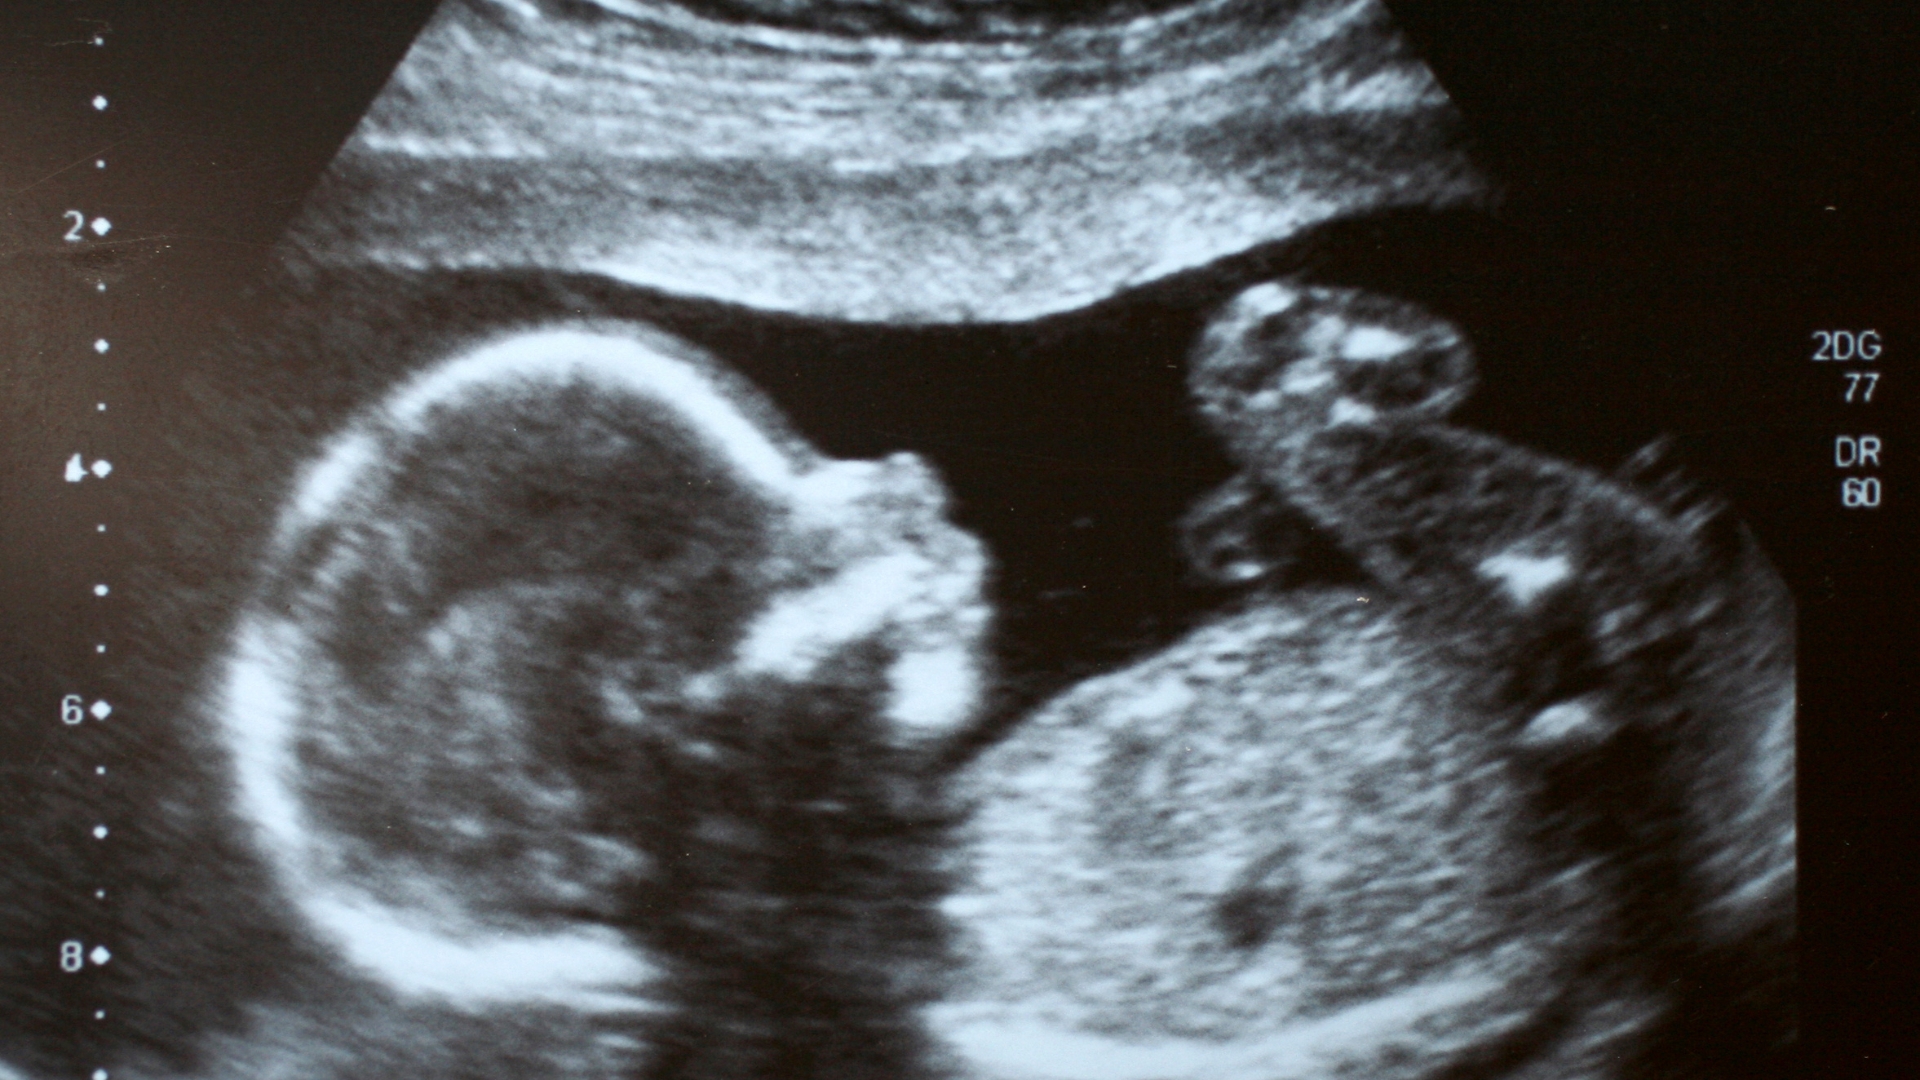

Siêu âm thai: Ước lượng cân nặng, kích thước vòng đầu, vòng bụng và chiều dài xương đùi.